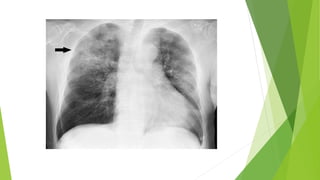

 Chest x-ray.

 Pulse Oximetry. Chest x-ray.  CT Scan.  Bronchoscopy  Thoracoscopy  Percutaneous aspiration/biopsy  Open lung biopsy